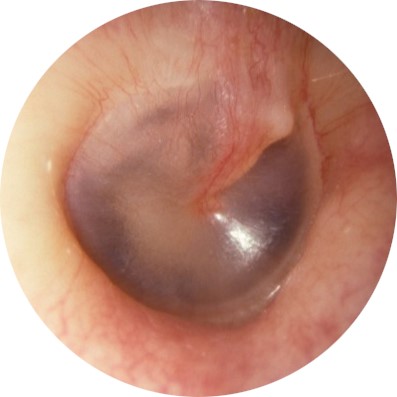

| TEED 1 |

Diffuse redness and retraction of tympanic membrane. Erythema over part of the tympanic membrane due to inflammation, particularly around the manubrium. |

|